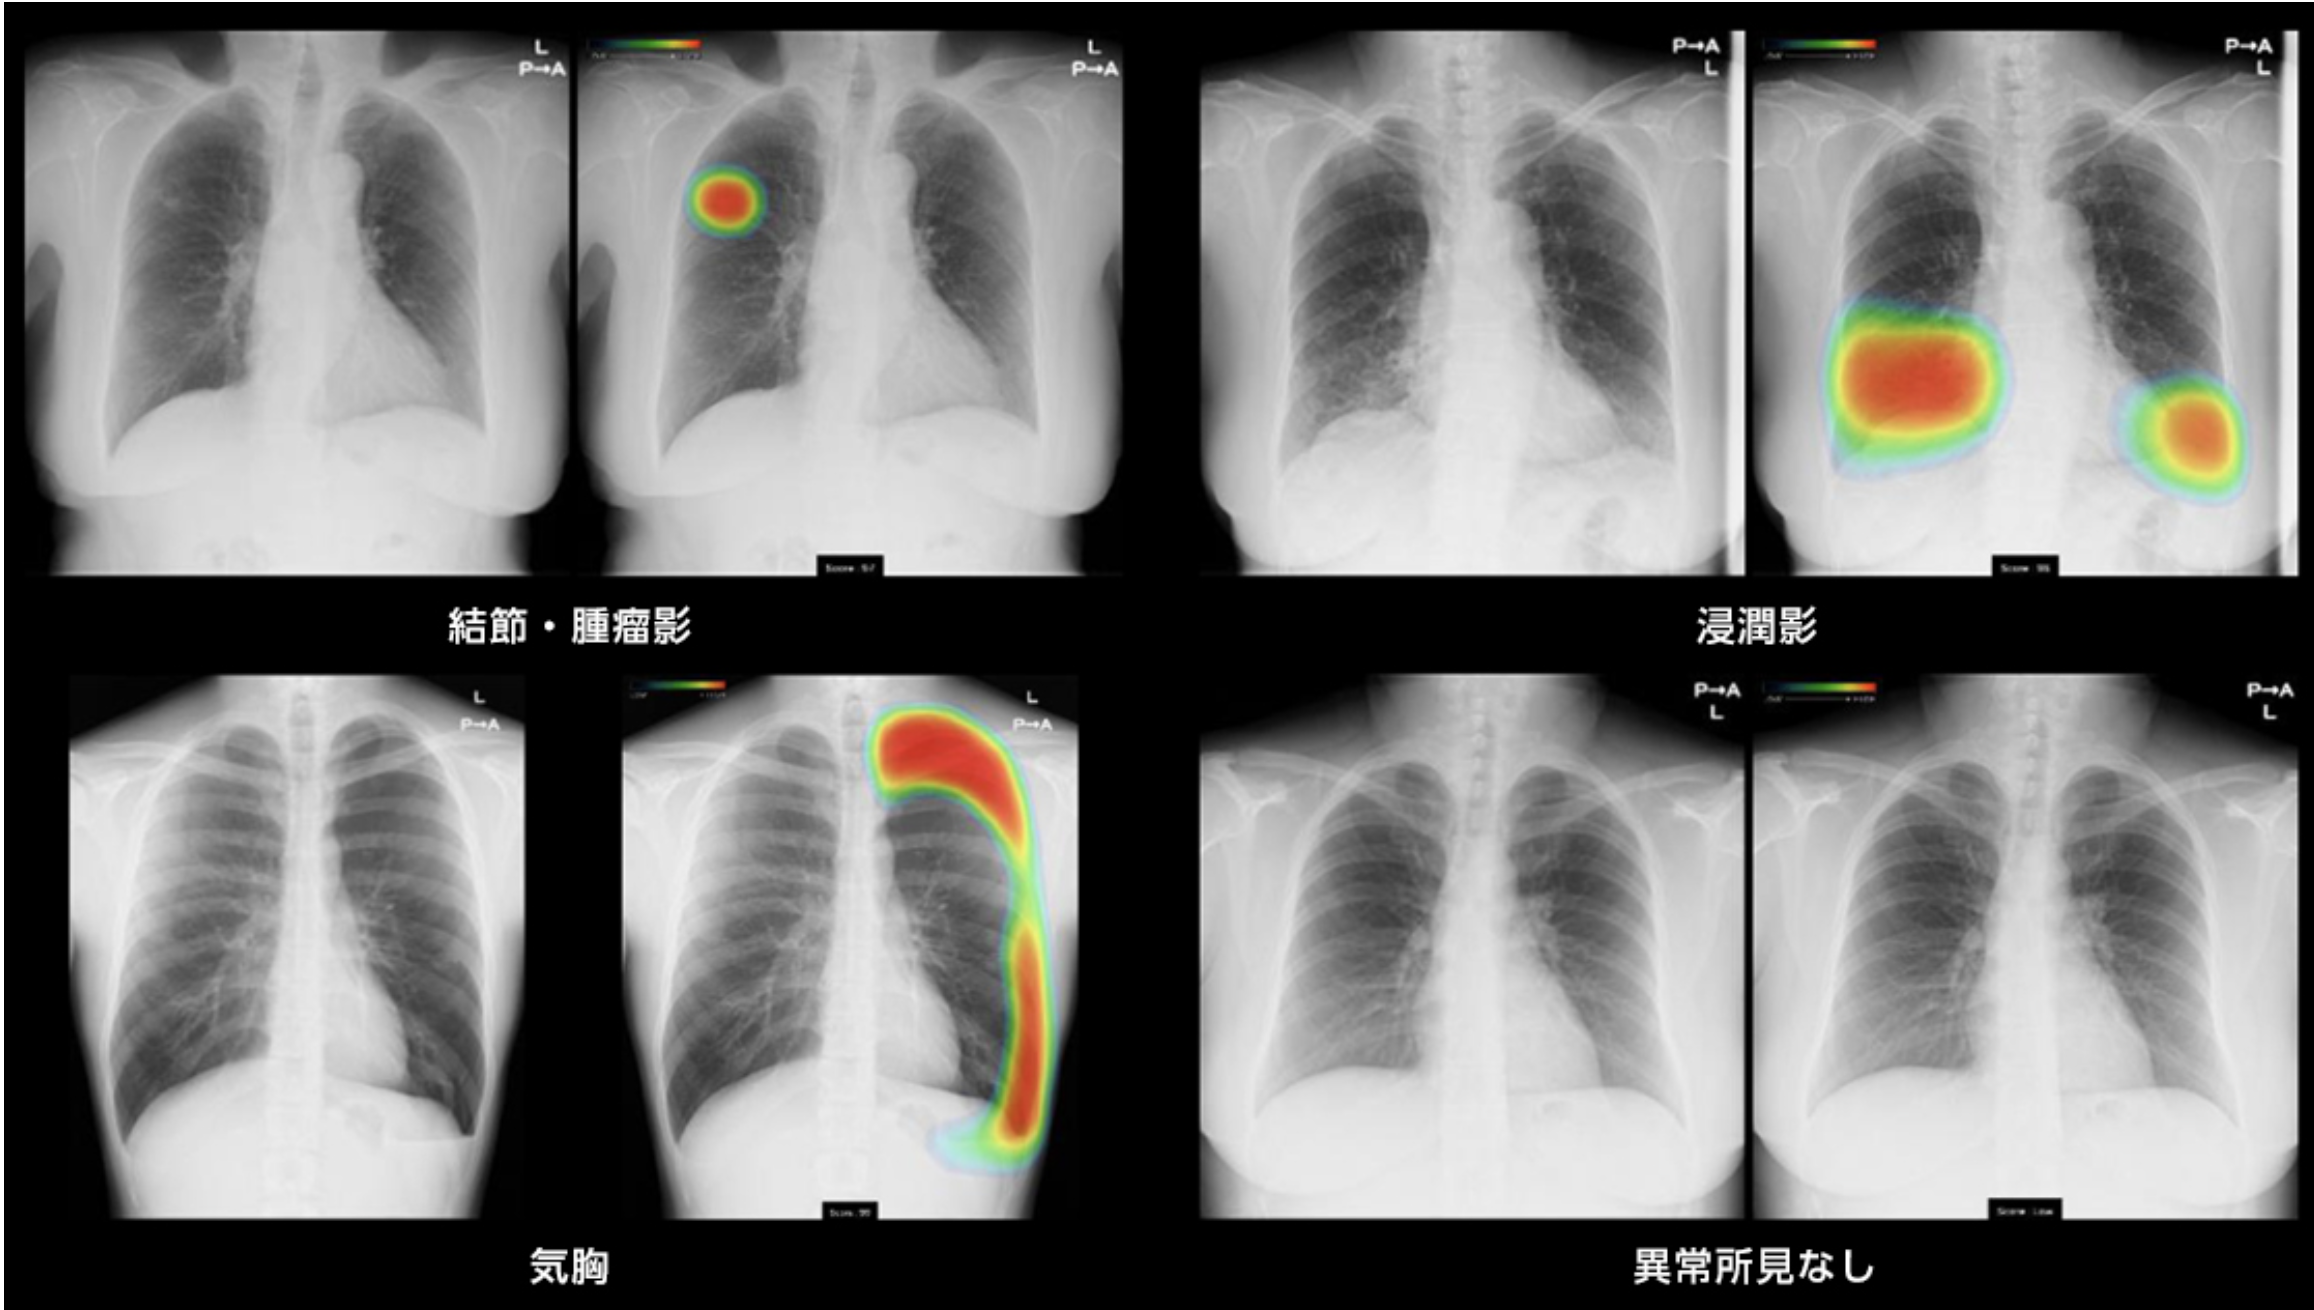

レントゲン異常

胸部レントゲンの異常を指摘された場合は、再検査が必要となります。

必要に応じて、胸部CT検査を行います。

AI診断支援機能

当院はAI診断支援機能があるレントゲン装置がございます。